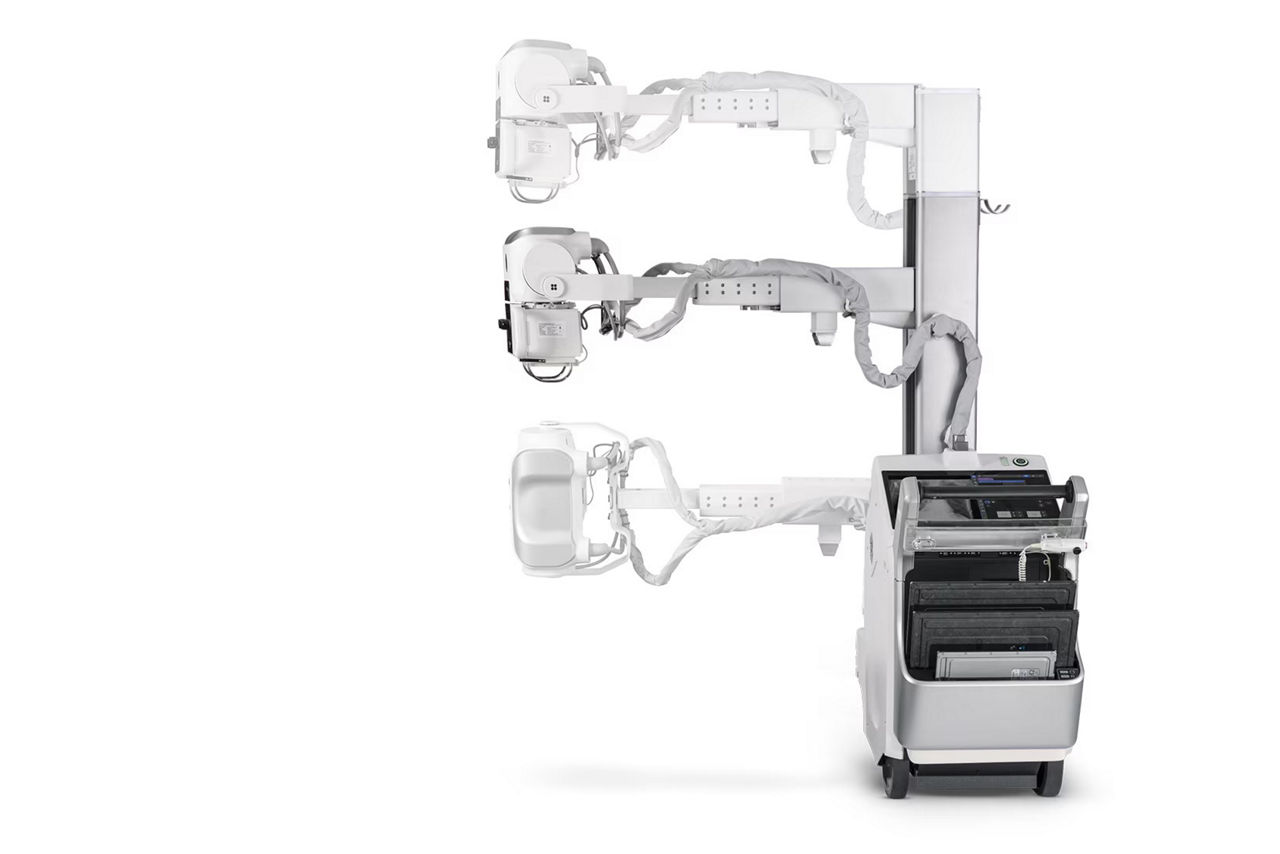

Free Motion telescoping column

Reduces lift force by up to 70%1 to help remove workflow stress and strain

Zero Click Exam

Eliminate the need for touchscreen interaction prior to annotation2

On-device AI

Automatically identifies critical conditions and provides onscreen quality checks